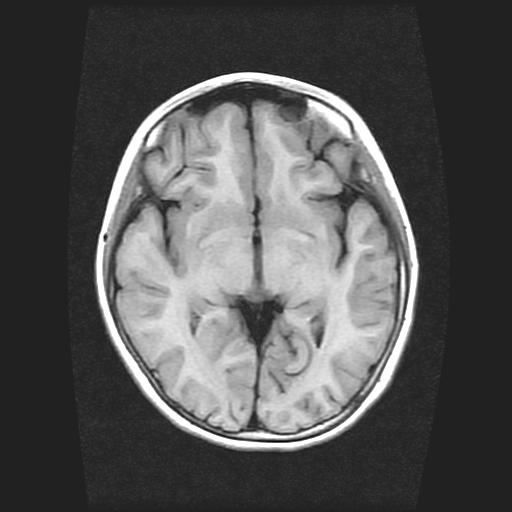

9岁女孩,三岁时诊断为癫痫,一直服丙戊酸钠,现患者一般情况良好,家长复查核磁片,看能否停药..

未见异常信号灶.

未发现异常信号。

停药要结合临床,如无发作可以停。